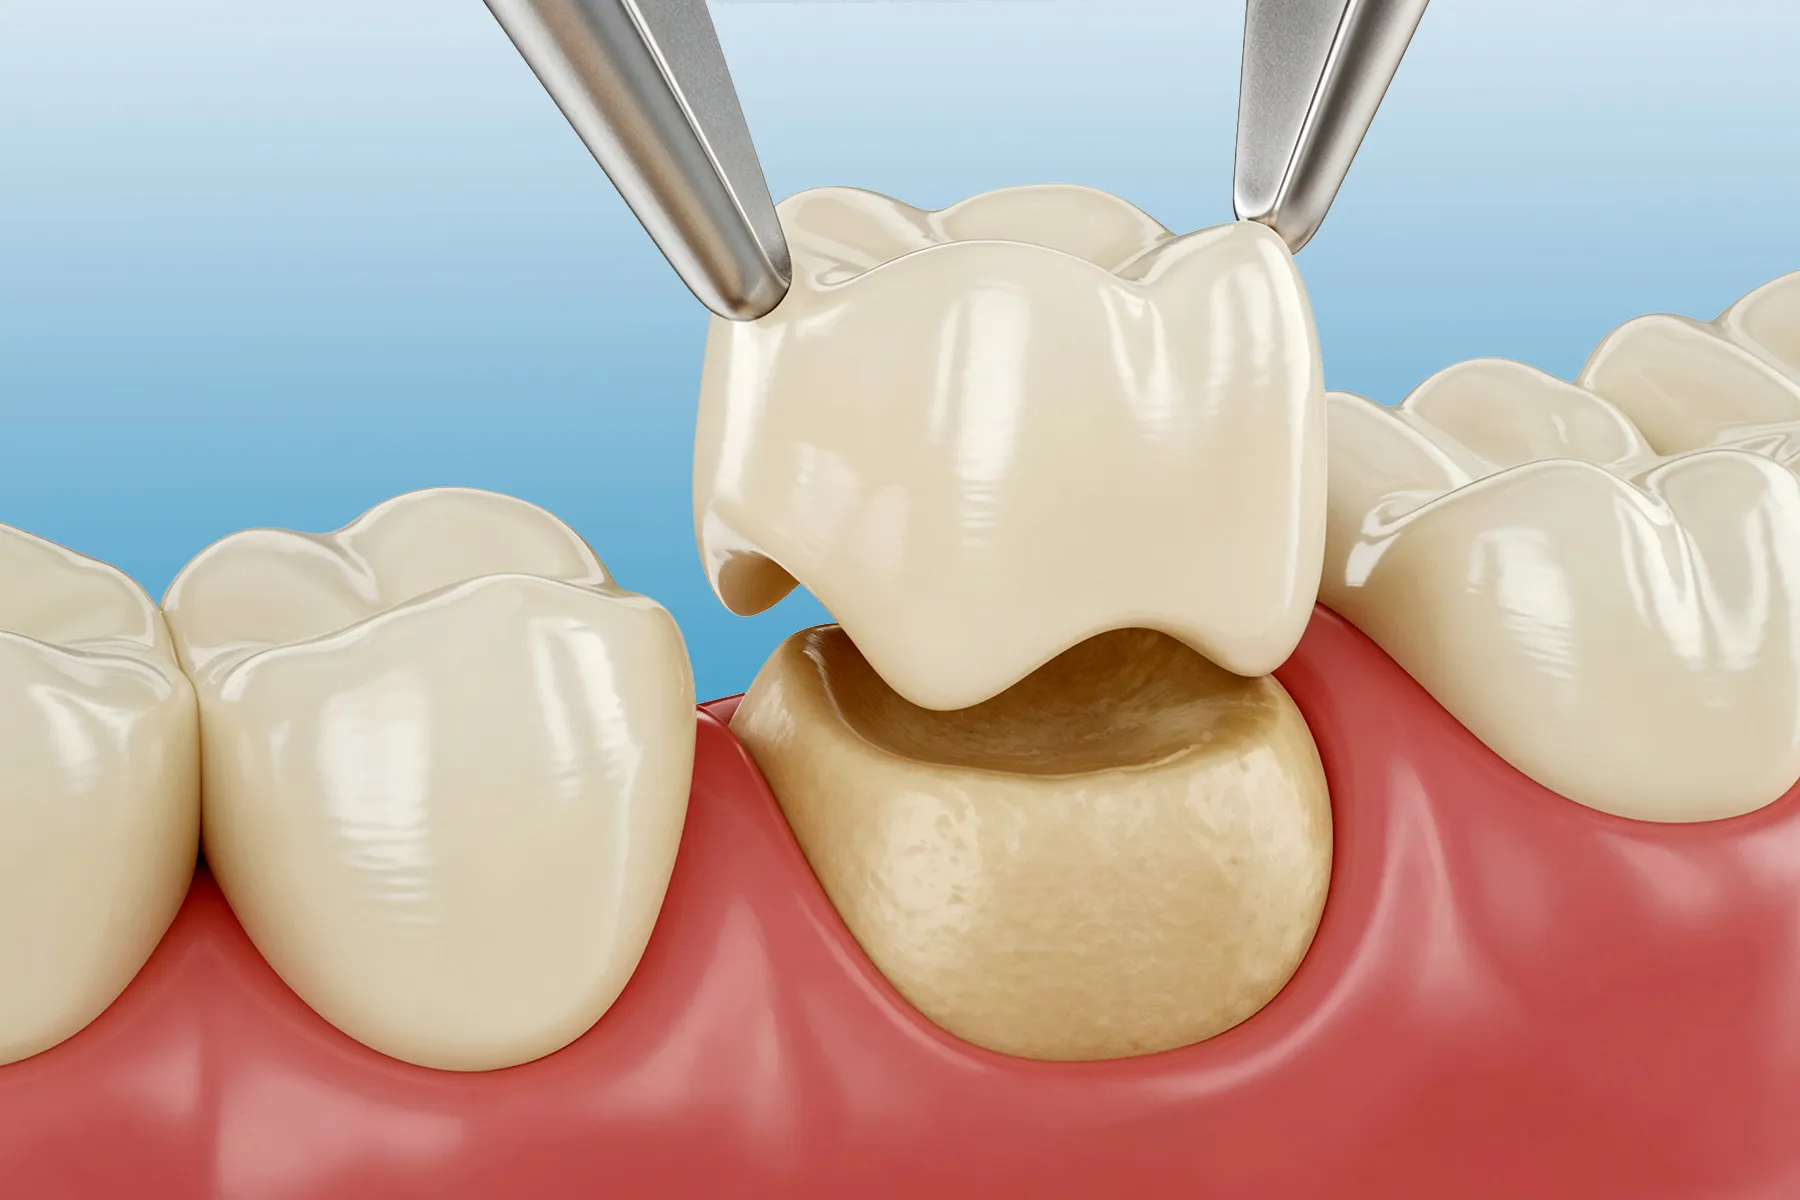

A dental crown is a custom-made cap designed to encase the entire visible portion of a damaged or weakened tooth. Crafted from premium materials like ceramic, zirconia, E-max, composite resin, or metal-infused porcelain, crowns restore not only the form and appearance of natural teethbut their full function, too.

Step 2: Tooth Preparation

Step 3: Fabrication (In-Lab or In-Clinic)

Step 4: Fitting & Bonding